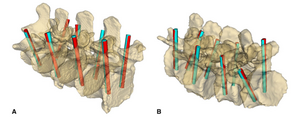

- 3.18 A Statistical Shape Model of the Human Second Cervical Vertebra